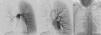

We present the case of a 19-year-old woman, smoker (8 pack-years), and regular cannabis user, with a history of severe bronchitis in childhood and frequent respiratory infections. She presented for episodes of coughing with hemoptoic expectoration since she was 15-years-old. The episodes were initially sporadic, but had become more frequent in recent months, sometimes occurring every 48h. On examination, she had decreased breath sounds in the right hemithorax, and acropachy. The chest radiograph showed loss of volume in the right lung and attenuation of the right hilum. The right pulmonary veins could not be identified on computed tomography (CT), and a diffuse increase in density was observed in the affected lung. Cardiac magnetic resonance imaging (MRI) ruled out associated heart disease, and the echocardiography ruled out pulmonary hypertension. Pulmonary arteriography was performed (Fig. 1A and B), in which hypoplasia of the right pulmonary artery and absence of right pulmonary venous return were observed. Arteriography of the thoracic artery (Fig. 1C) showed right bronchial artery hypertrophy originating in the descending aorta. Lung function test results were: FEV1: 2.040 (75.5%), FVC: 2.800 (90.1%) and DLCOc SB: 69.3%. Varices were observed in the distal trachea and start of the right main bronchus on fiber optic bronchoscopy. Considering the previous findings, we opted for surgical treatment, specifically, right pneumonectomy. The immediate post-operative period was uneventful, and the patient is currently asymptomatic.

Pulmonary arteriography showing hypoplasia of the right pulmonary artery, providing little perfusion, almost entirely limited to the upper lobe (A), in which right venous drainage cannot be seen (B). Arteriography of the thoracic aorta showing an irregular, winding bronchial artery with origin in the anterior superior side of the descending thoracic aorta (C).